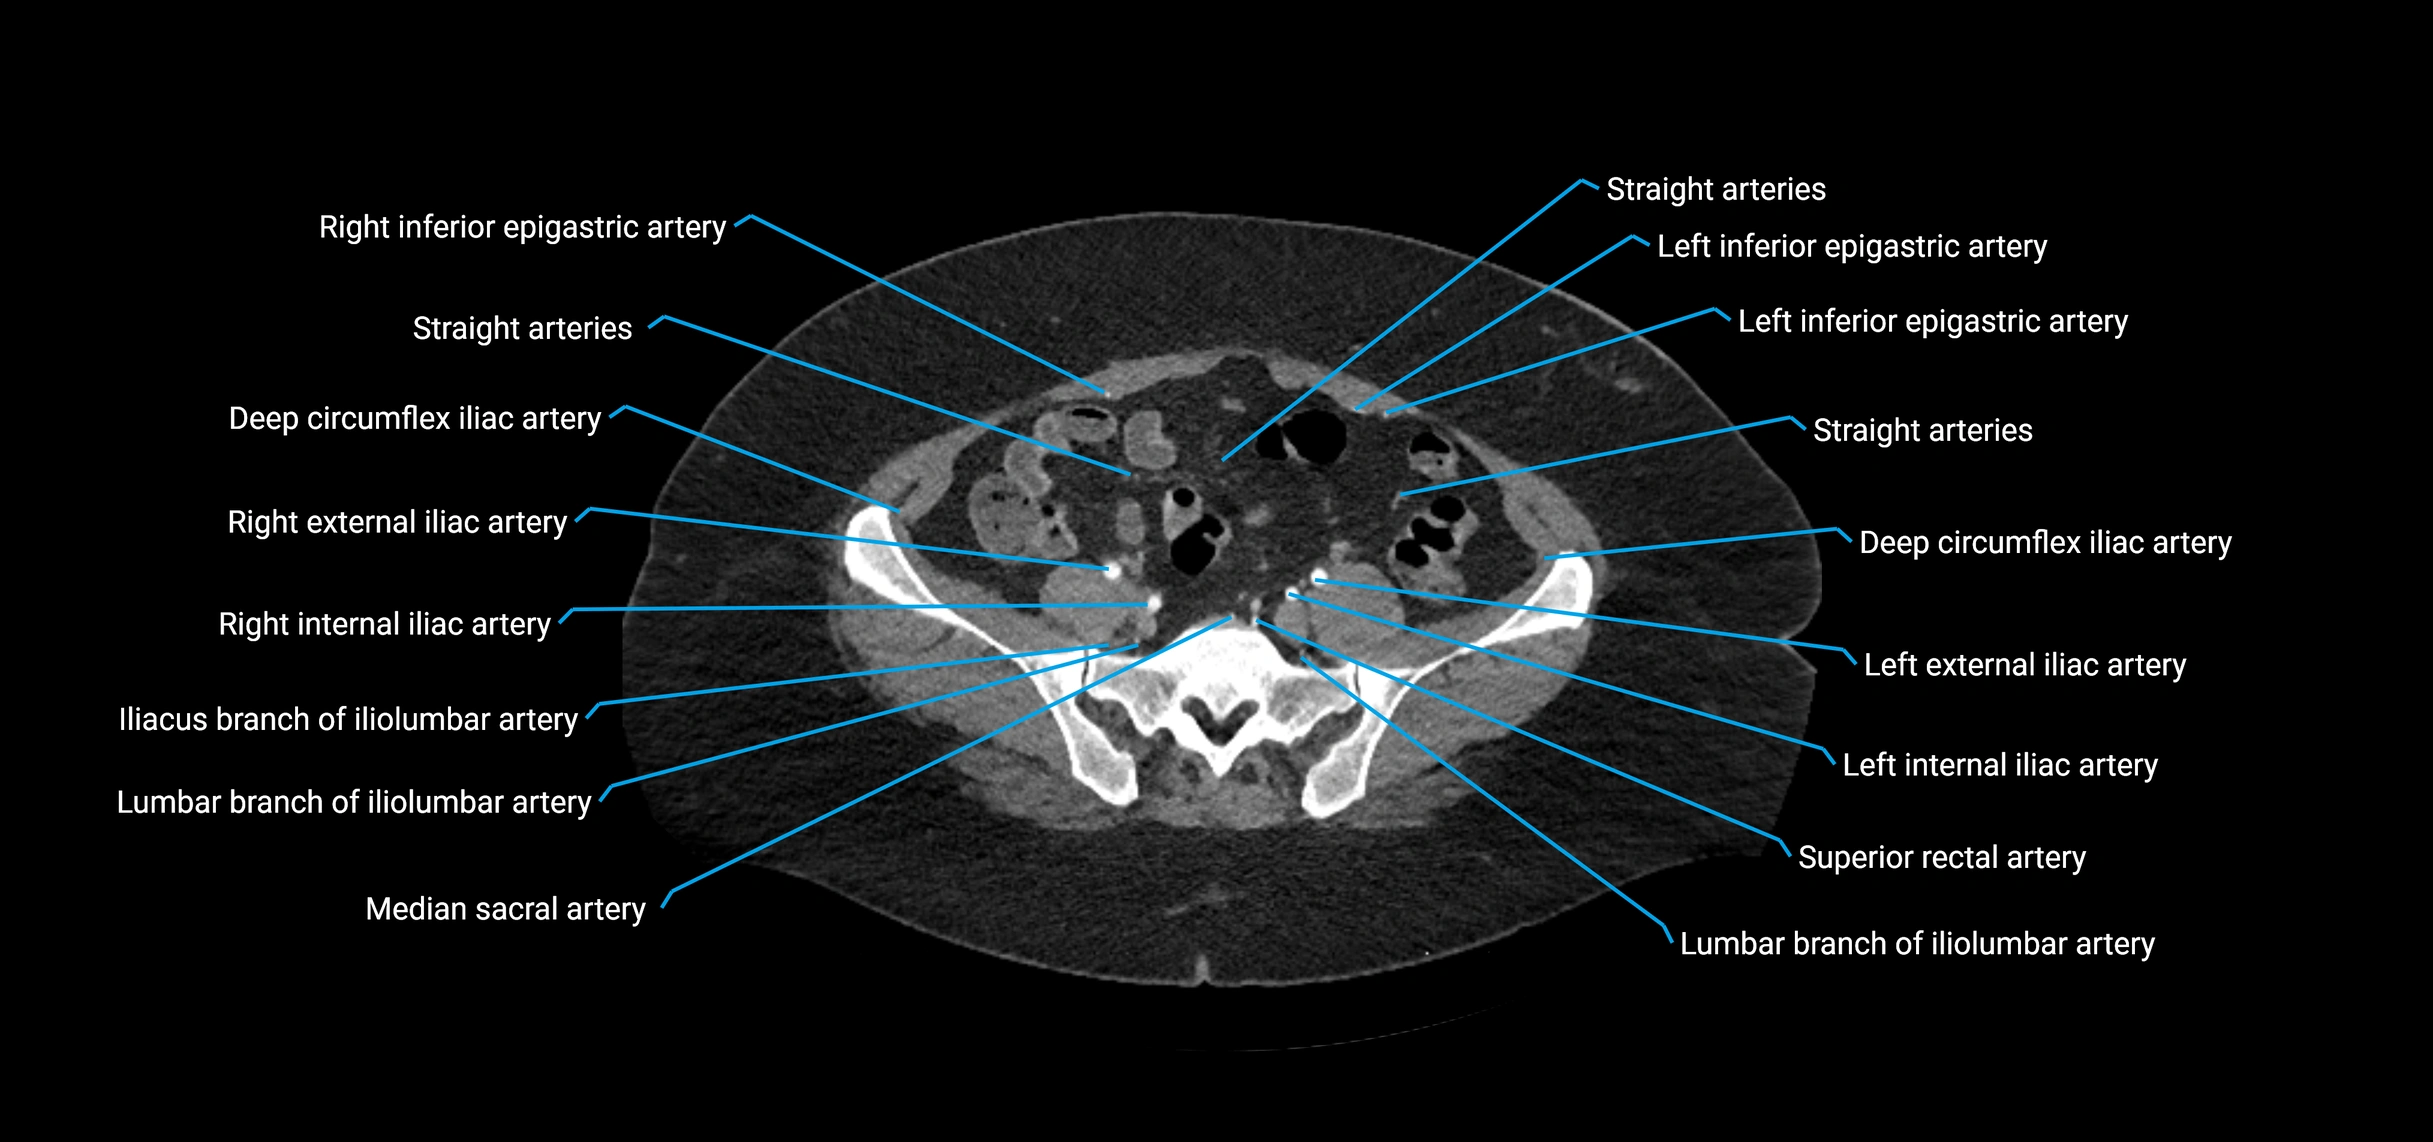

CT images

image

Contrast-enhanced CT (CTA):

• Gold standard for abdominal aortic imaging

• Provides excellent detail of lumen, wall, aneurysm, thrombus, and branch vessels

• Multiplanar and 3D reconstructions help in aneurysm measurement, stent graft planning, and dissection evaluation